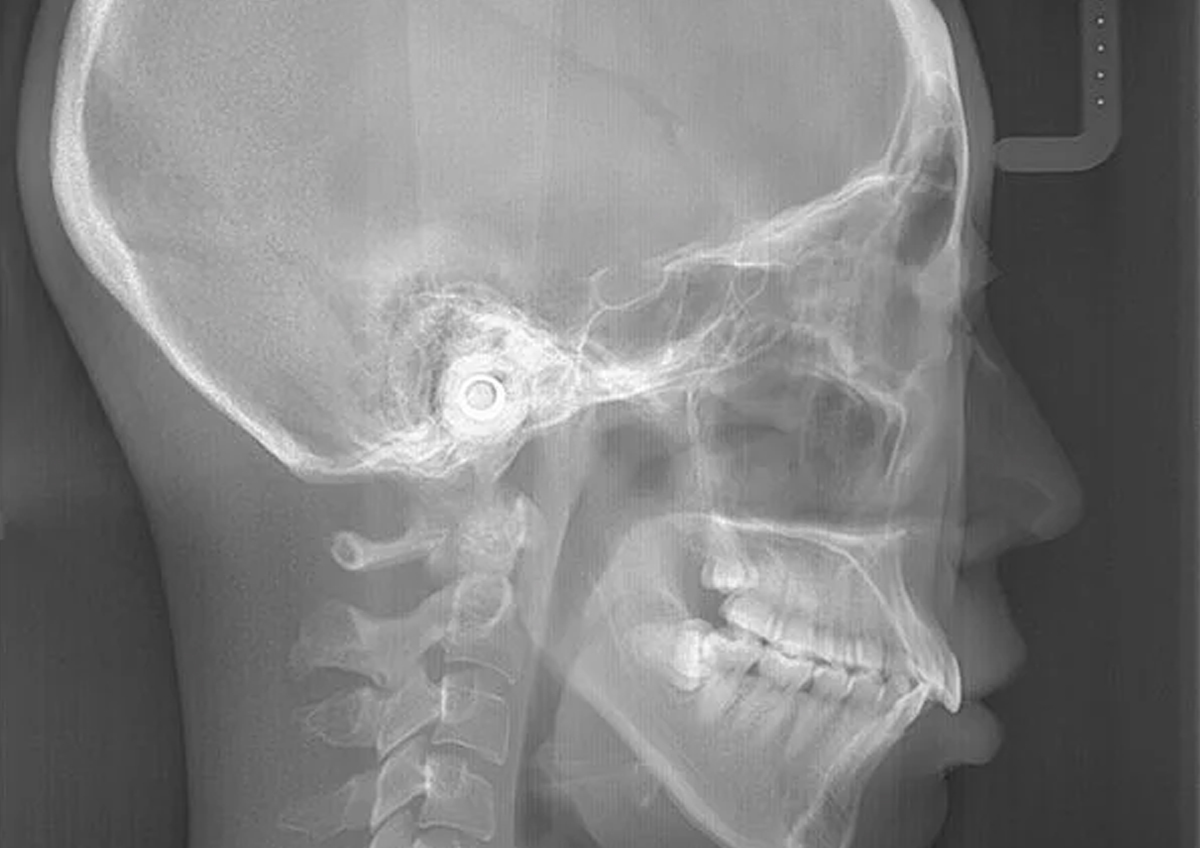

診断に必要な歯の型を採取し、お顔やお口の中の写真、パノラマレントゲン写真、頭部X線規格写真(セファログラム)など、診断・治療計画を立てるために必要な検査を行います。